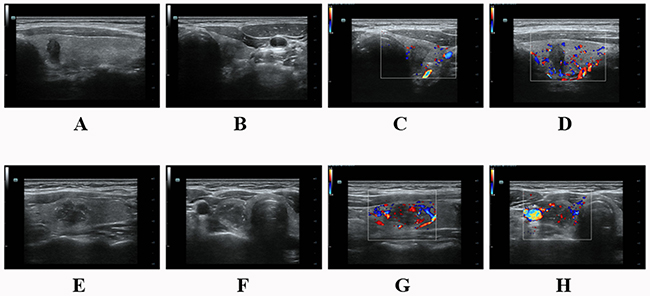

All grayscale and Doppler sonographic examinations were performed with 5–13MHz linear probes (ESAOTE Mylab90 and Mindray Resona 7) by experienced radiologists. US scanning involved the evaluation of the neck anatomy, including the thyroid gland, surrounding vasculature, and cervical lymph nodes. Images of each suspicious nodule or lymph node were obtained in both transverse and longitudinal orientations. All images were recorded and uploaded to a picture archiving and communication system for later retrospective analysis. The sonographic parameters of the target nodule included echogenicity, internal architecture, location (upper-, mid-, low-third, anterior, middle, posterior and throughout the anterior and posterior of thyroid lobe in longitudinal section; internal, middle, external and throughout the internal and external of thyroid lobe in transverse section), size (anteroposterior diameter (A), longitudinal diameter (L), transverse diameter (T) and the greatest dimension), shape (A/T≥1 and A/L≥1), margin (regular and irregular, the latter was specifically defined as infiltrative, microlobulated or spiculated), presence of microcalcification or not and color Doppler signal (none/low and medium/high) (Figure 6). PTMC was defined as a tumor that is 10 mm or less along its greatest dimension. Features suggesting abnormal metastatic lymph nodes included enlargement in short axis, loss of the fatty hilum, a rounded rather than oval shape, hyperechogenicity, cystic change, calcification, and peripheral vascularity [12]. For patients with multiple nodules, only the most suspicious nodule corresponding to the pathological outcome was included. The time interval between US and operation for PTC tissue was within one month with the median time of 8 days. All the sonographic features were assessed by one researcher on the premise of not knowing the pathological results.

Figure 6: (A-D) A 37 year-old male PTC patient without LNM. There was a hypoechoic solid nodule on the right lobe with an irregular margin and taller than wide shape. The size was 6.9mm×10.0mm×5.8mm. No calcification was detected in the nodule. Color-Doppler showed low blood flow. (E-H) A 34 year-old female PTC patient with LNM. There was a hypoechoic solid nodule on the left lobe with an irregular margin and microcalcification. It located throughout the internal and external of the thyroid lobe with A/L<1 and A/T<1. The size was 14.1mm×13.2mm×18.4mm. Color-Doppler showed low blood flow. (A&E) Nodule throughout the anterior and posterior of thyroid lobe in longitudinal section. (F) Nodule throughout the internal and external of thyroid lobe in transverse section.